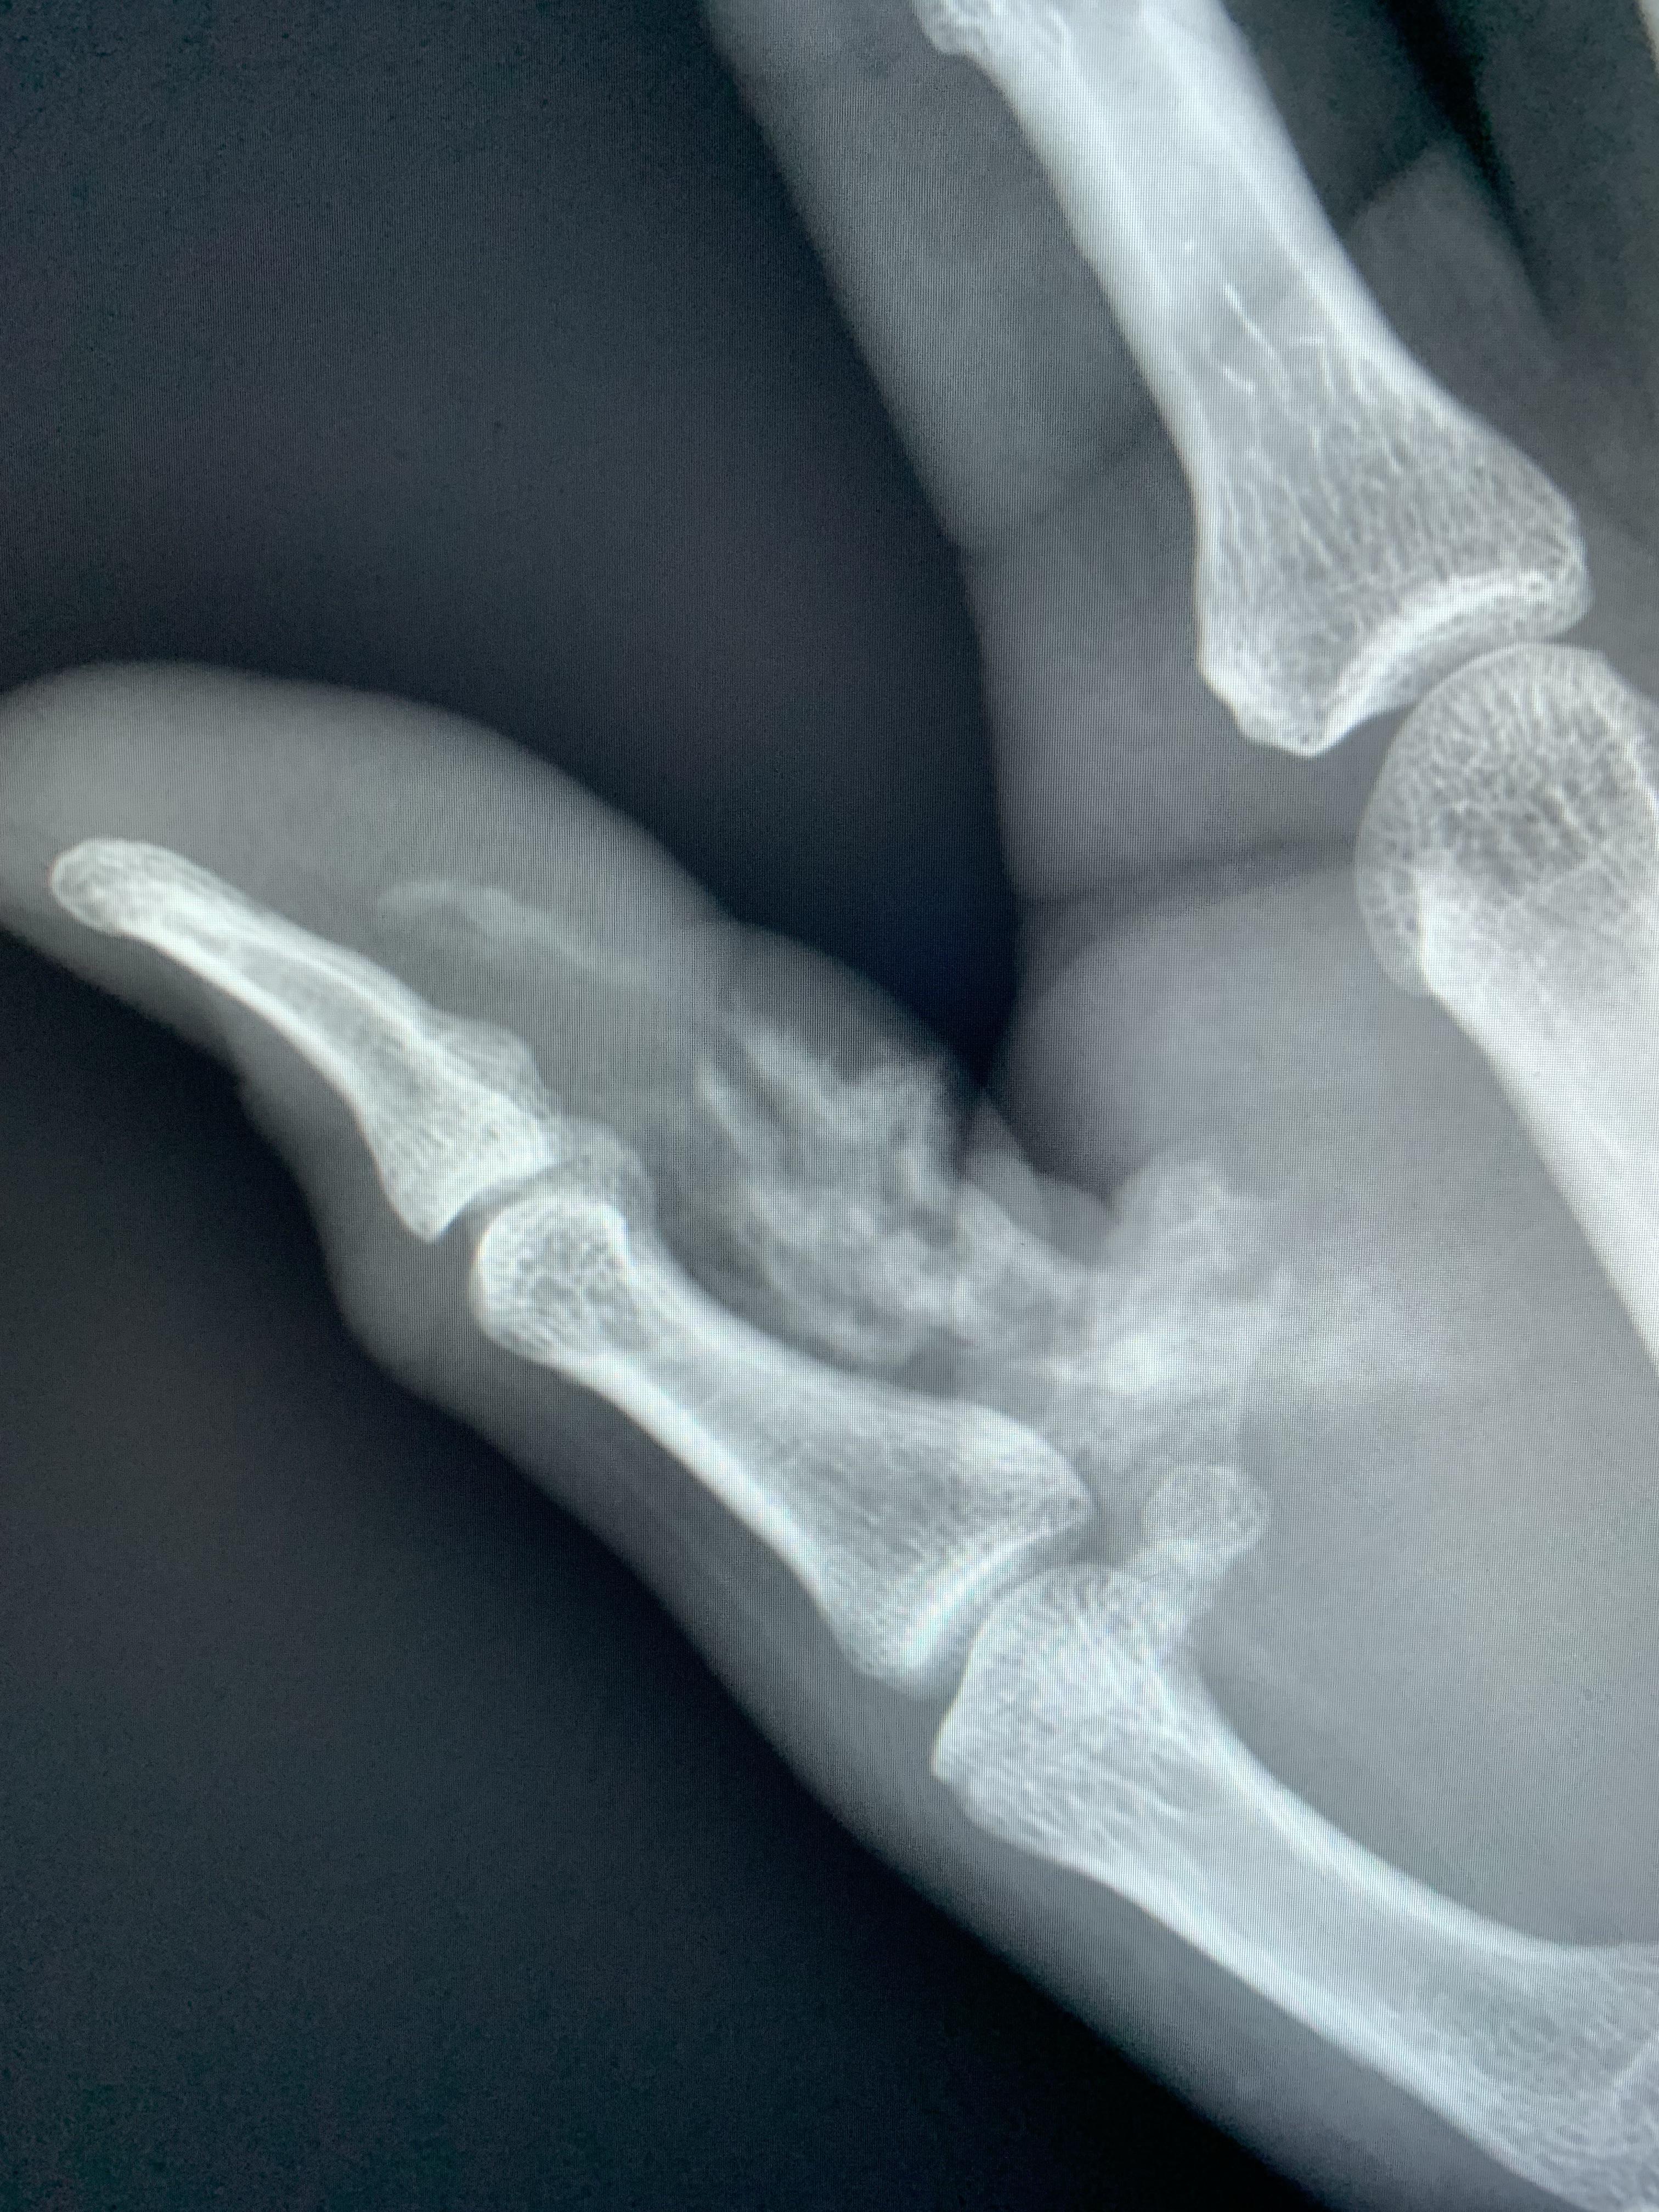

Paint Gun Injection Injury . The injected substance leads to extensive tissue damage and sometimes to loss of the limb.

The injected substance leads to extensive tissue damage and sometimes to loss of the limb.

High pressure paint gun injection r/Radiology Paint Gun Injection Injury The injected substance leads to extensive tissue damage and sometimes to loss of the limb. Paint Gun Injection Injury.